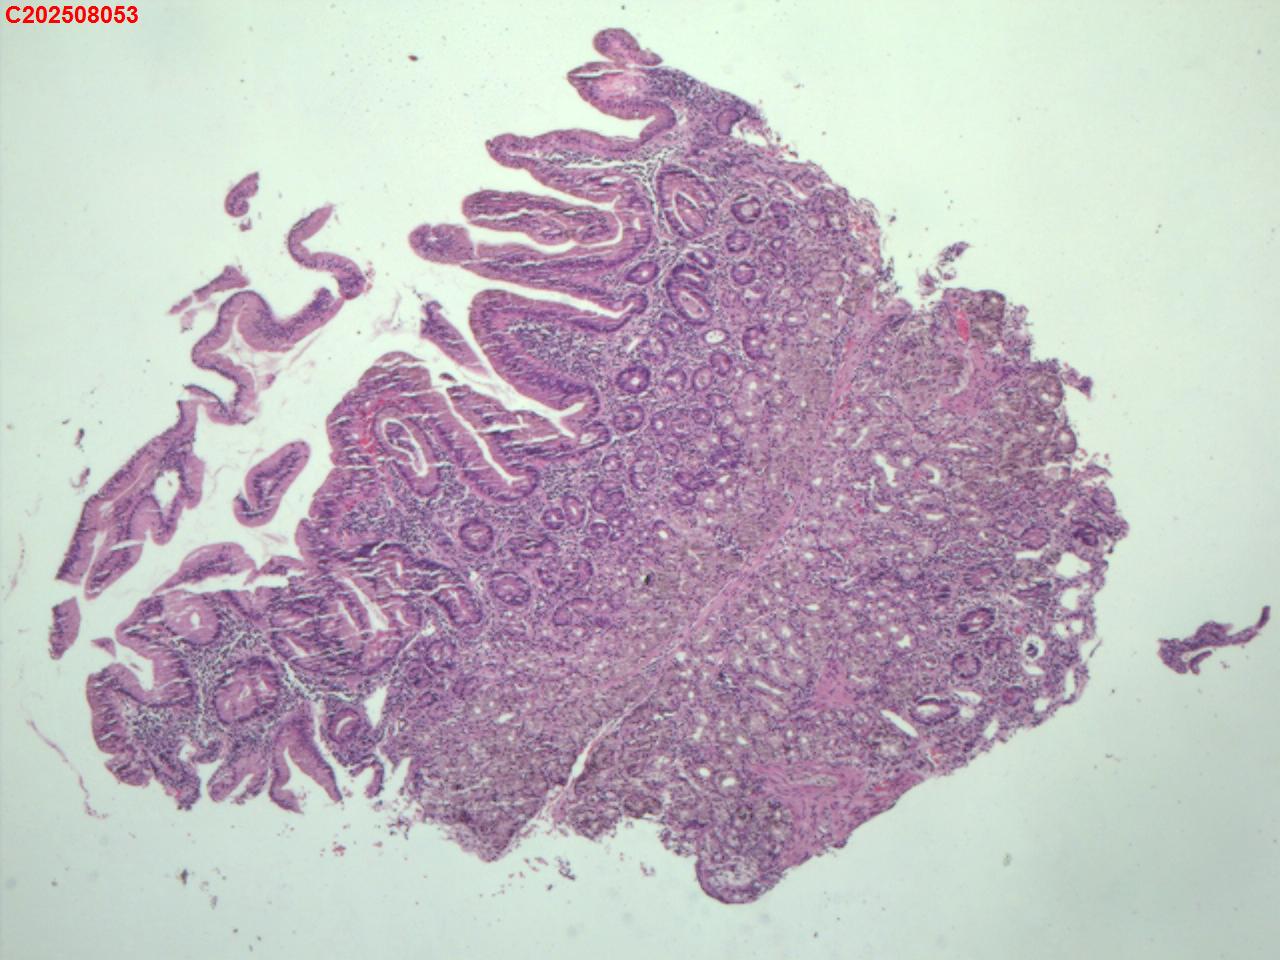

十二指肠黏膜

十二指肠球部息肉

十二指肠球部黏膜

十二指肠球部可见一息肉样隆起。

图1

增生性息肉。